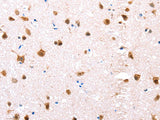

Applications IHC

IHC 1:100-1:300